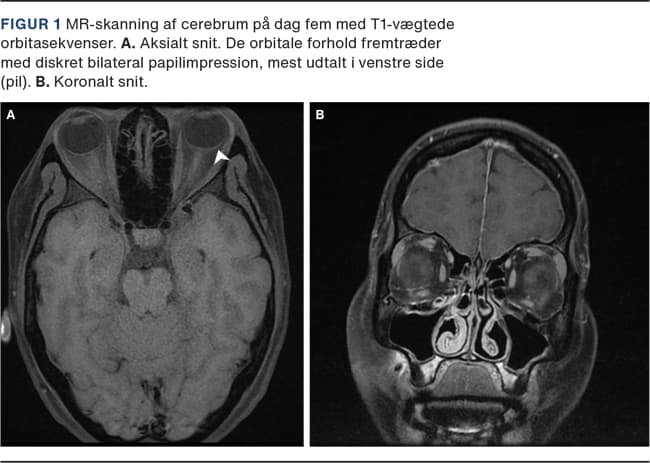

MR-skanning af cerebrum på dag tre var normal og uden empty sella, breddeøgede nn. optici-skeder, tortuøse nn. optici og stenose af sinus transversus. MR-skanning af cerebrum med orbitasekvenser på dag fem viste diskret venstresidig papilimpression (Figur 1A).